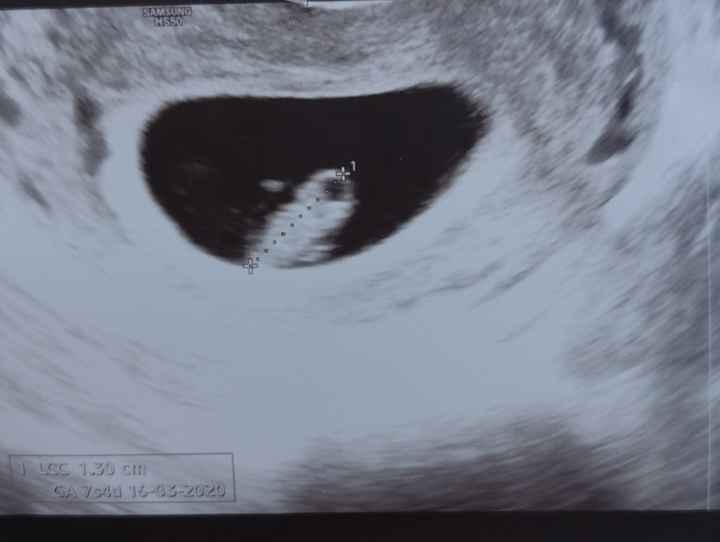

Secondo voi ragazze?Metodo Ramzi pareri 3

Metodo Ramzi pareri 4che mi dite ragazze??

Metodo Ramzi pareri 511 settimane... che mi dite?

Hai l’attacco del cordone a sinistra

Allora dico fiocco azzurro

Eco interna 7+4